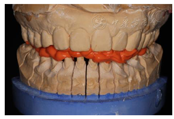

首先对上颌牙进行牙体预备,将诊断蜡型的硅橡胶成型阴模切片,指导前牙预备。牙体预备完成后,制取硅橡胶印模,灌制工作模型。于备牙过程中逐步去除

垫、制取颌位记录以转移咬合关系,使用成型阴模加临时冠桥树脂材料将蜡型Mock up至口内,作为临时修复体(图24,图25,图26,图27,图28,图29,图30,图31)。